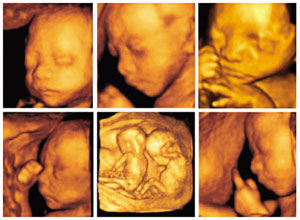

也就是说,三维彩超是图片,是静态的,四维彩超是录像,是动态的,可以让孕妈妈看到胎儿一连串的动作,能更清晰的显示胎儿信息完成排畸。

彩超其实还是黑白的,而三维、四维彩超在做出三维、四维图像的时候才可能是土黄色,也并非彩超就是彩色的。被称为彩超,是因为会用彩色标注心脏、血流等指标。

四维彩超可以立体显示胎儿的脸部、各器官的发育情况,甚至胎儿在母体里的状态也可以观察到;对胎儿畸形,如唇裂、腭裂、骨骼发育异常、心血管畸形等能早期诊断。

三维彩超只能是某个时间点上的照片,只能观察五脏六腑是否畸形,排除结构畸形,并不能对胎儿运动系统做出排畸检测。